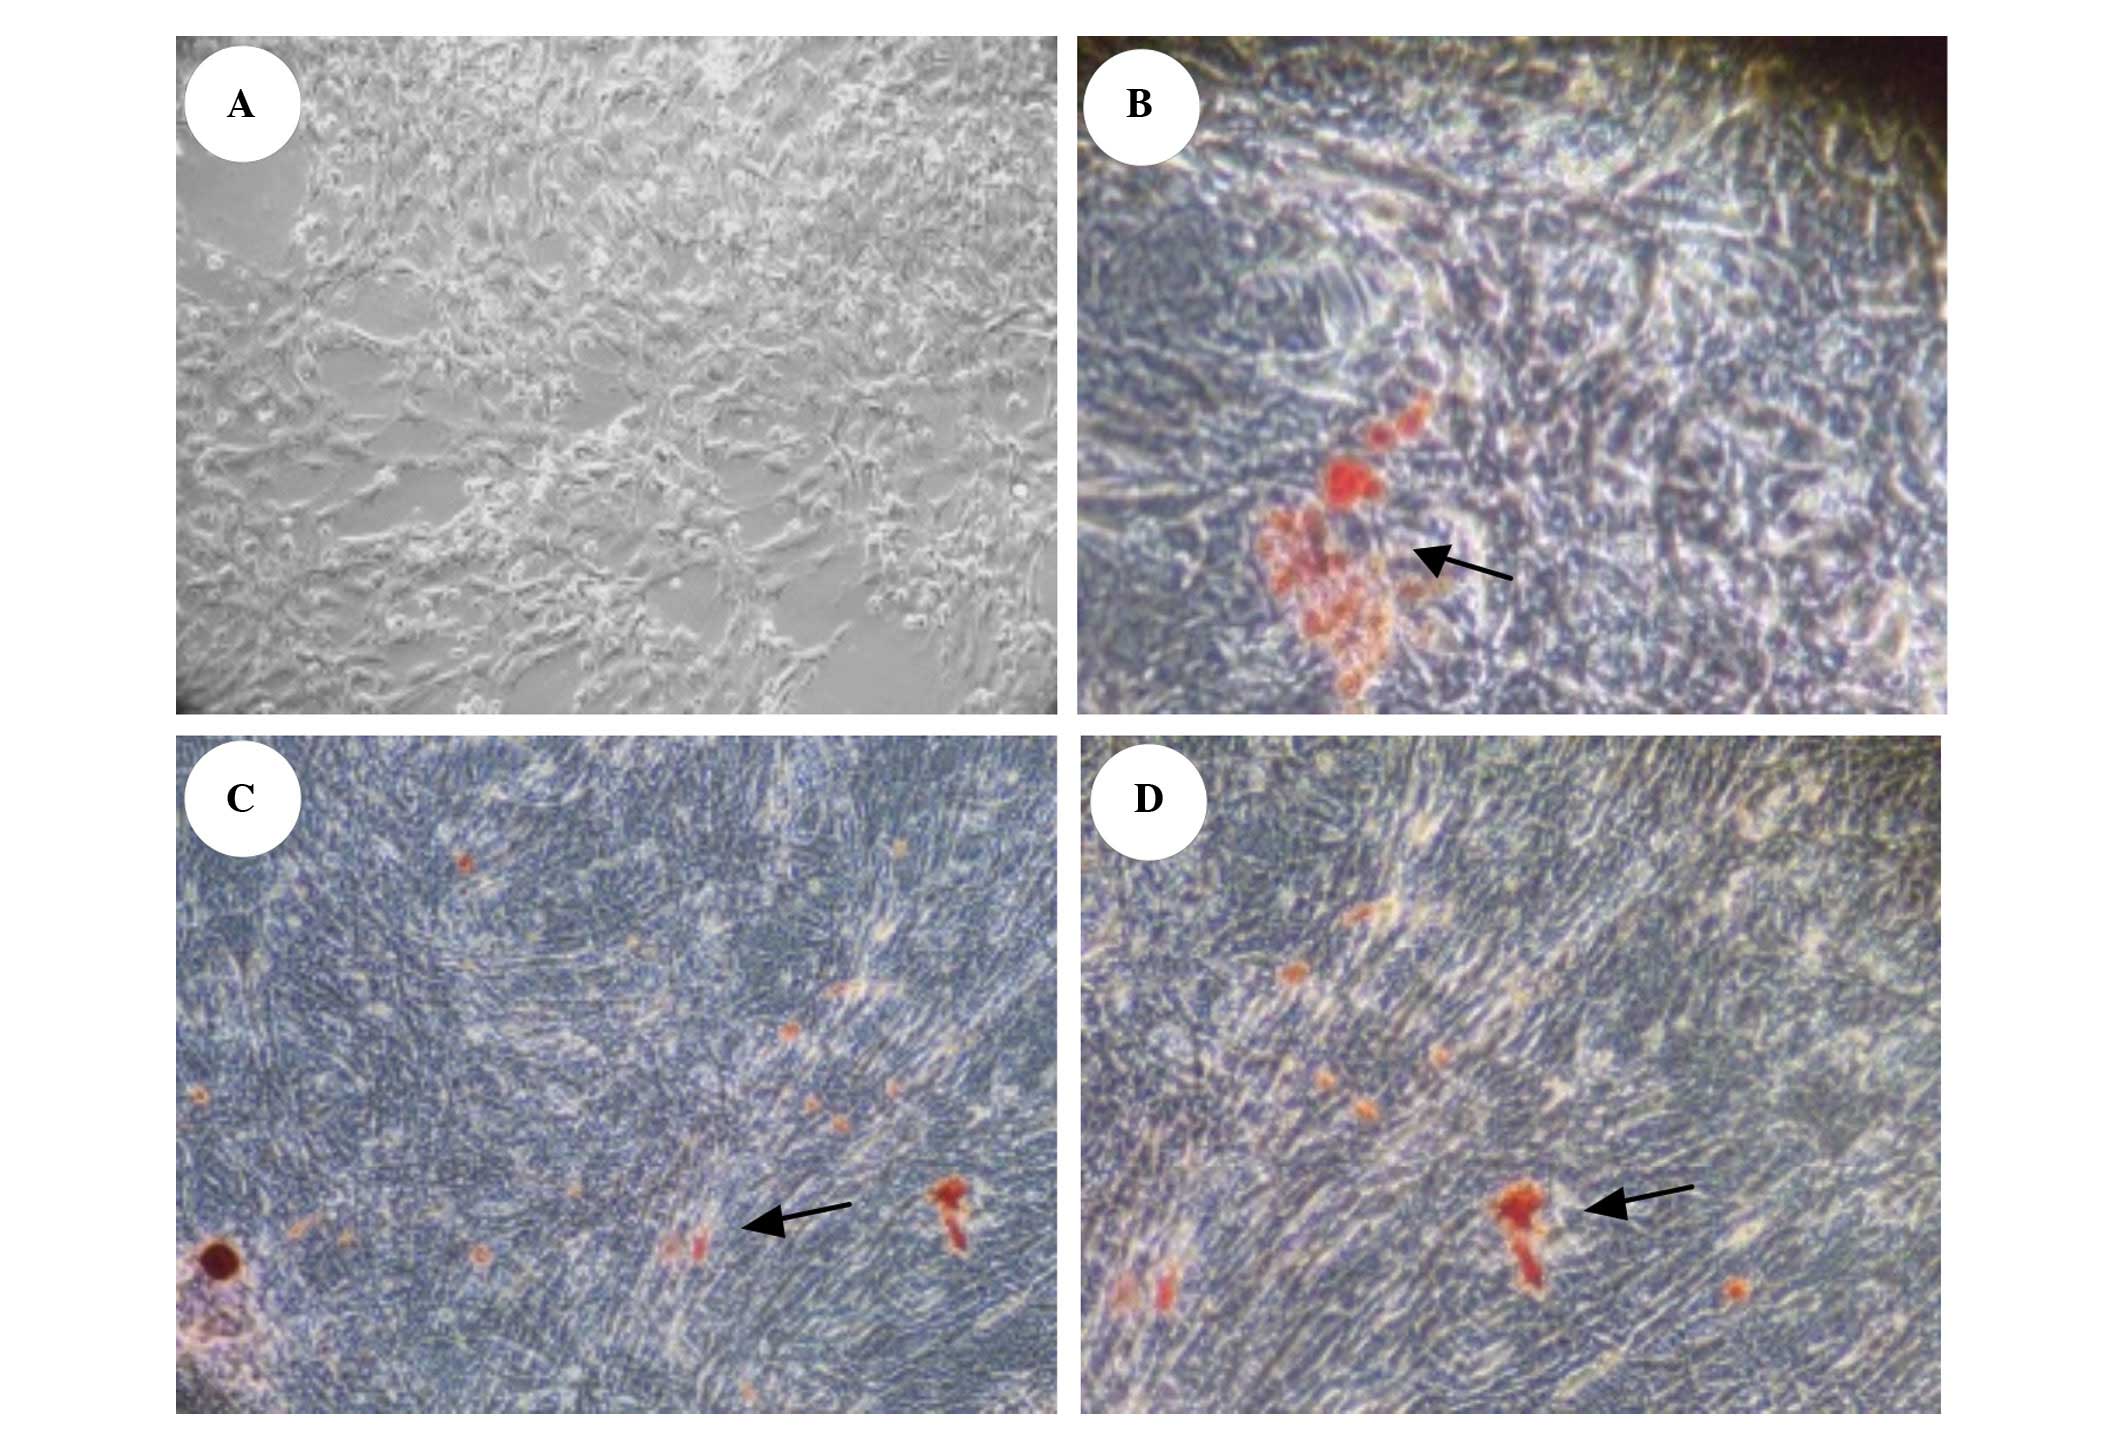

Alizarin red staining (ARS)

For ARS, cells were washed twice with

phosphate-buffered saline (PBS) and fixed with formalin at room

temperature for 10 min. Formalin was removed and the wells were

washed twice with PBS and once with distilled water. The ARS

solution was then added and incubated at room temperature for 30

min. Finally, the wells were washed with distilled water until the

background staining on the negative wells (wells containing MSCs)

was fully clear. Cells were examined under an inverted optical

microscope (Nanjing Jiangnan Novel Optics Co., Ltd., Nanjing,

China).

No calcium salt deposition was observed in VSMCs at

day 6 of transfection in the normal group; large amounts of

orange-red calcium salt deposition was observed in the ALD and

negative transfection control groups. Calcium salt deposition in

the siRNA transfection group was observed to be significantly

reduced (Fig. 5).